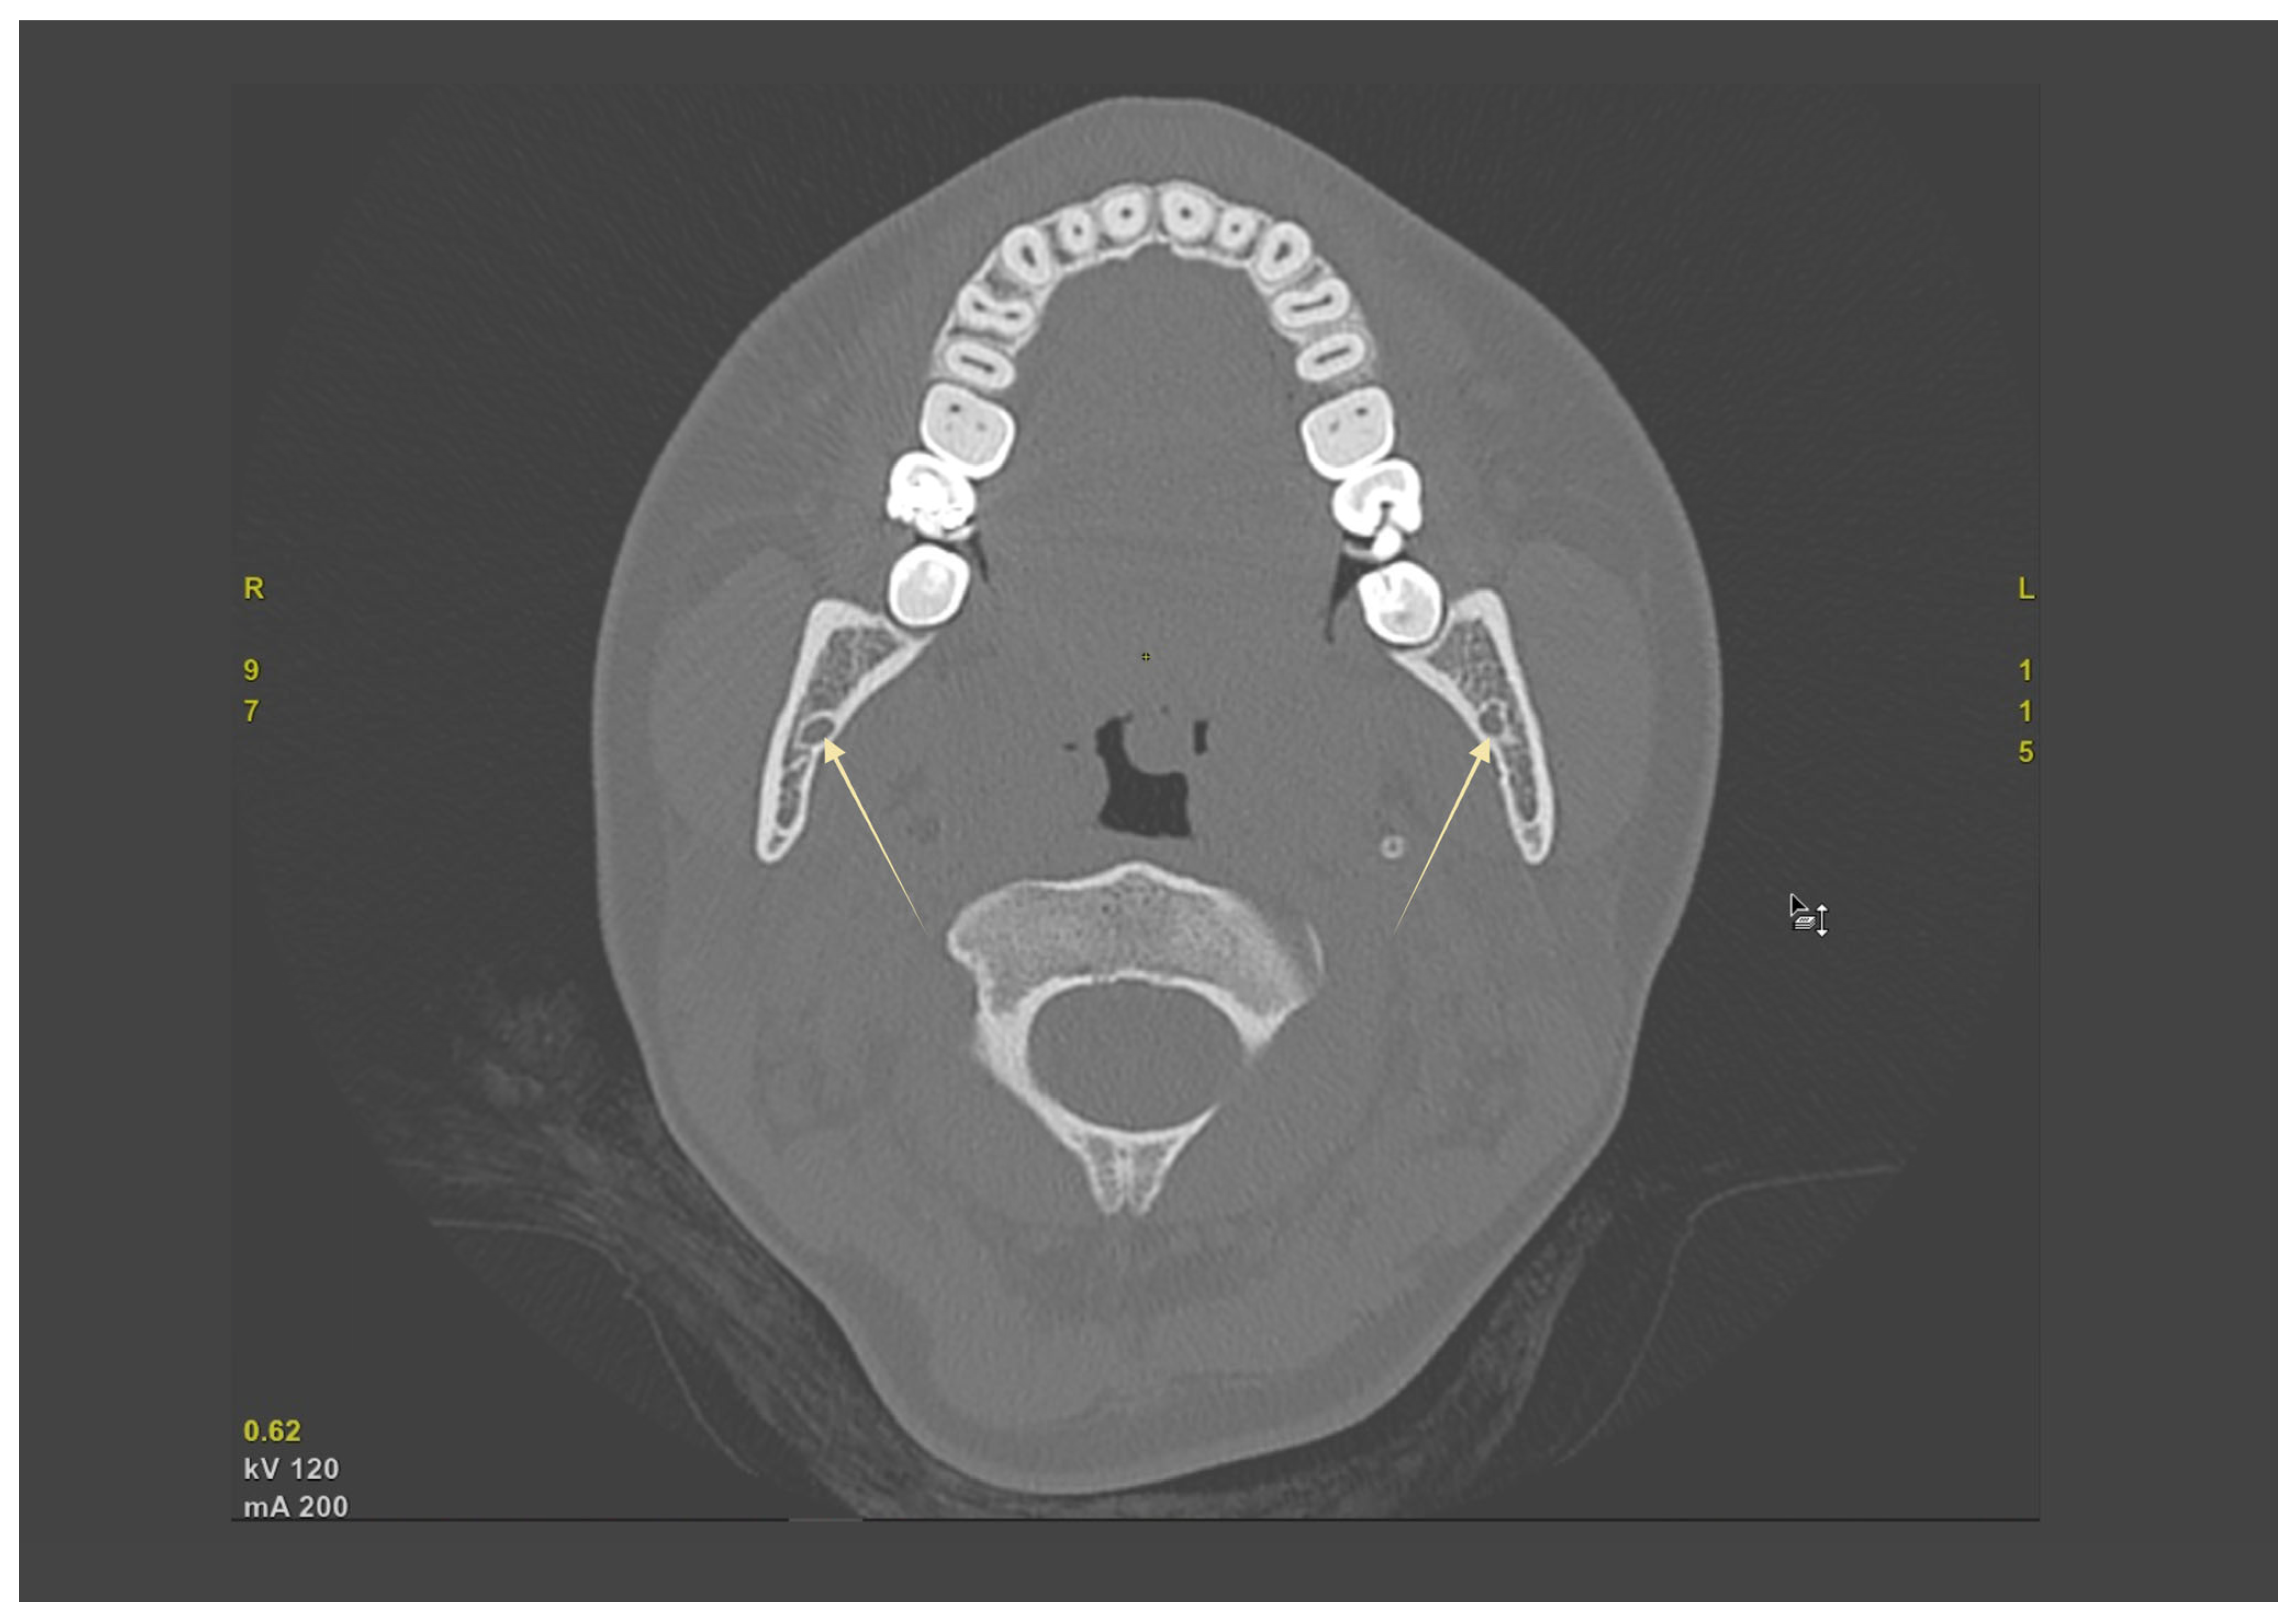

Across CBCT cohorts, BMC prevalence typically ranged from single-digit to low double-digit percentages, with extremes explained by definition and voxel size. Trifid canals were uncommon (≈1–2%). PR consistently underestimated canal branching compared with CBCT. Clinical implications for local anesthesia, osteotomy planning, and hemostasis are summarized in Table 2; study-level prevalence and definitions appear in Table 1. In practice, axial CBCT is useful for screening bifid or retromolar branches and for bilateral comparison (Figure 3).

Figure 3. Axial CBCT demonstrating the mandibular canal (MC) bilaterally. Corticated cross-sections of the mandibular canals (yellow arrows) are visible within the mandibular bodies on both sides, allowing direct assessment of canal morphology and symmetry.